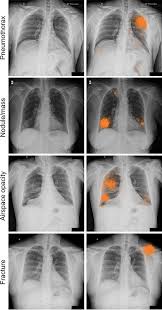

Patchy Airspace Opacification In The Left Retrocardiac Region With Download Scientific Diagram

Deep Learning For Chest Radiograph Diagnosis A Retrospective Comparison Of The Chexnext Algorithm To Practicing Radiologists